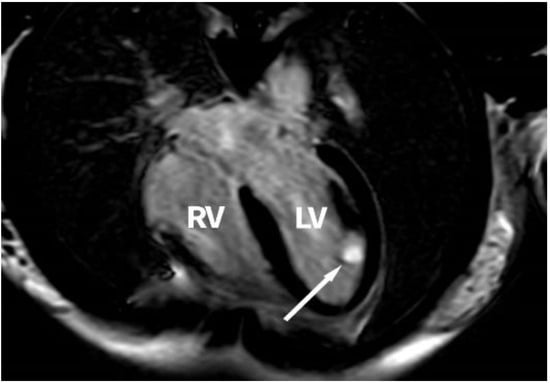

The CMRI performed showed a tumour mass of 18/14/12 mm located inside the LV, at the base of the anterior papillary muscle, in contact with the lateral wall, with well-defined margins, partially mobile, with no evidence of an intraventricular obstructive effect, with homogenous T1 and T2 isointense signals, on the myocardial perfusion sequence with a lower perfusion rate than that of the myocardium, with late oncoming, intense and homogenous enhancement after the management of contrast agent on the LGE sequences, the tumour mass not presenting malignancy characteristics. Figure 2 presents a cardiac magnetic resonance image of the tumour.

Figure 2. Cardiac magnetic resonance image of the tumour in the left ventricle and papillary muscle at the base of the anterolateral papillary muscle (white arrow, left ventricle tumour); RV, right ventricle; LV, left ventricle.